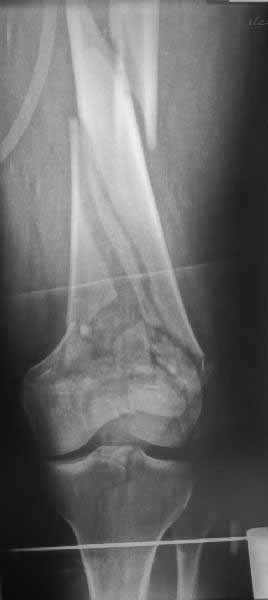

Ответ на эту часть Вашего поста – вложенный файл. Больная оперирована неделю назад по поводу открытого перелома дистального эпиметафиза бедренной кости. После операции она идёт в рентгенкабинет для выполнения послеоперационной контрольной рентгенографии, представленной на слайдах 10 и 11. Узнав, почему её фотографируют, просила передать Вам, Антон, привет.

наружный мыщелок не дорепонироавн - это приводит к вальгусной деформации оси коленного сустава, очень критично для последующей функции.